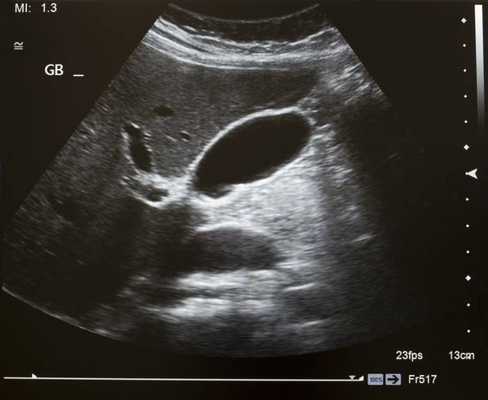

![]()

УЗИ брюшной полости в норме- размер, форма и структура органов брюшной полости (печени, поджелудочной железы и селезенки) не нарушены;

- контуры органов четкие, ровные, капсула дифференцируется хорошо;

- разрастание ткани и жидкость в брюшной полости отсутствуют;

- диаметр аорты в норме, стенки не изменены;

- желчный пузырь без изменений, камни отсутствуют, протоки не расширены;

- почки нормальной бобовидной формы, без присутствия камней, нарушение оттока мочи не обнаружено.